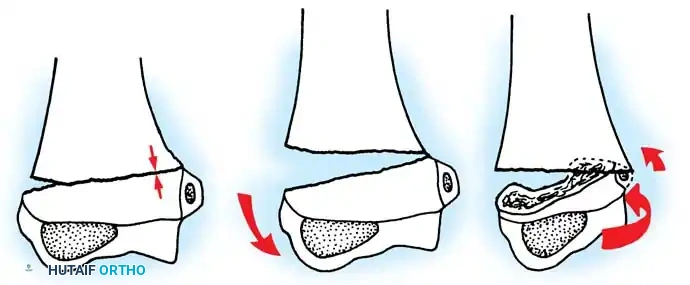

Fractures can present as angulated, translocated (shifted), or totally displaced. In the context of an elbow dislocation, the proximal fragment may become loose within the joint space or trapped, acting as a mechanical block to reduction.

Fig. 33-40 Examples of angulation, translocation, and total displacement of radial neck fractures.